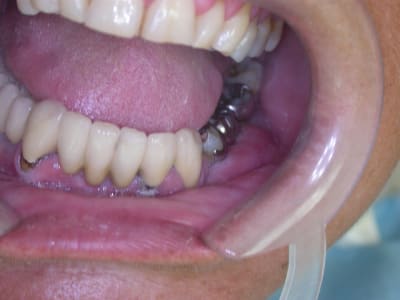

Faut lui dire de changer sa méthode de brossage...Elle a de superbes mylolyses (ou régler le problème de bruxisme si bruxisme il y a ). :))

Non pas de bruxisme, juste un brossage horizontal très certainement. Mais franchement ça n'est pas le plus grave dans sa cavité buccale.